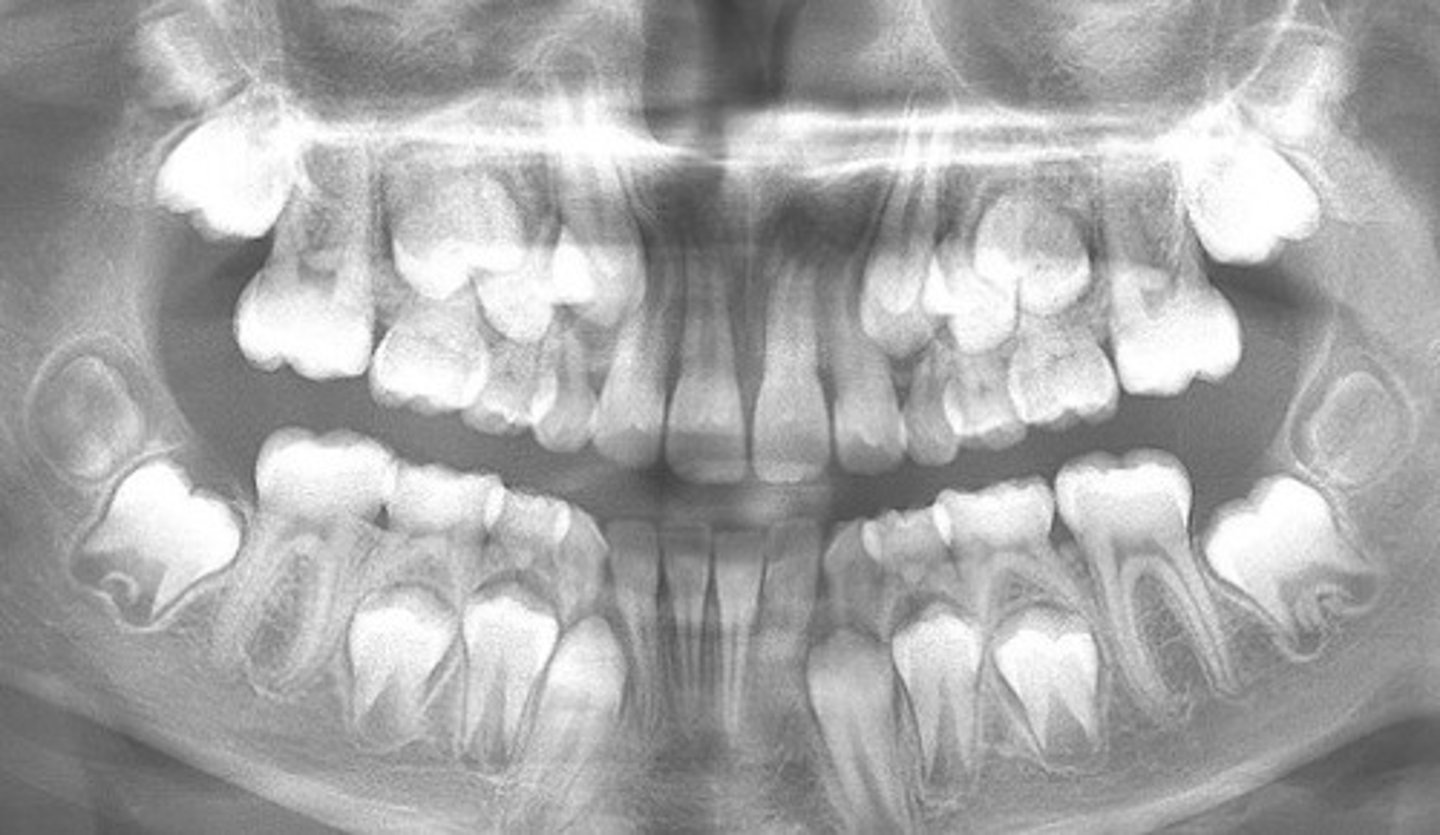

8 years old

How old do you think this child is?

<p>How old do you think this child is?</p>